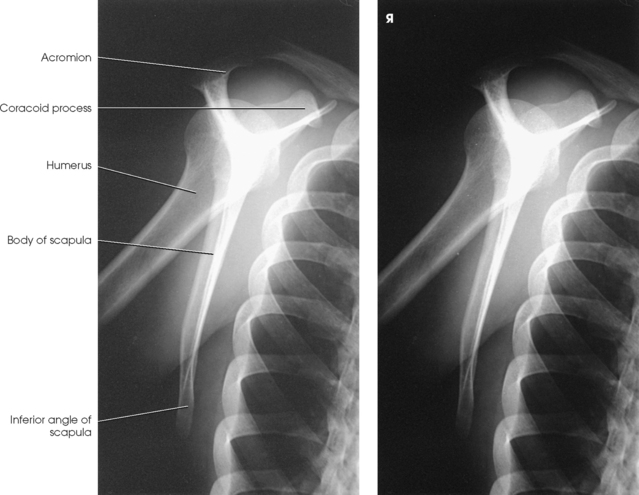

Structures shown: The image shows the bony and soft structures of the shoulder and proximal humerus in the anatomic position (Figs. 5-14 to 5-16). The scapulohumeral joint relationship is seen.

Fig. 5-14 A, AP shoulder, external rotation humerus: greater tubercle in profile (arrow). B, AP shoulder, neutral rotation humerus: greater tubercle (arrow).

Fig. 5-15 AP shoulder, internal rotation humerus: greater tubercle (arrow); lesser tubercle in profile (arrowhead).

Fig. 5-16 A, AP oblique projection of right shoulder without use of compensating filter. B, AP projection of same patient with compensating filter. Note improvement of visualization of bony and soft tissue areas with filter.

External rotation: The greater tubercle of the humerus and the site of insertion of the supraspinatus tendon are visualized (see Fig. 5-14, A).

Neutral rotation: The posterior part of the supraspinatus insertion, which sometimes profiles small calcific deposits not otherwise visualized (see Fig. 5-14, B), is seen.

Internal rotation: The proximal humerus is seen in a true lateral position. When the arm can be abducted enough to clear the lesser tubercle of the head of the scapula, a profile image of the site of the insertion of the subscapular tendon is seen (see Fig. 5-15).